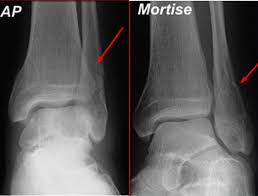

For some reason, no one seems to like lateral knees, especially students. Lateral malleolar fracture with deltoid injury or bimalleolar or trimalleolar fracture. 687 x 522 png 292 кб. The other two are the lateral and the posterior malleolus. Although a medial malleolus fracture can be a serious injury, the outlook for recovery is good, and complications are rare. The medial malleolus is the largest of the three bone segments that form your ankle. The lateral malleolus provides key stability against excessive eversion of the ankle and foot. Radiograph showing lateral malleolus fracture.

Radiograph showing lateral malleolus fracture. Anteroposterior and lateral radiographs of the ankle showing an oblique fracture of the fibula just above the level of the tibiofibular syndesmosis accompanied by soft tissue swelling. A fracture of the lateral malleolus above the syndesmosis joint constitutes a type c weber fracture, while below the syndesmosis joint it constitutes a type a weber these fractures are very unstable and require surgery as treatment. Causes, symptoms, and diagnosis of bimalleolar fractures. Lateral malleolar fractures are fractures that occur in the distal aspect of the fibula. Here's what you need to know. It is a part of the bone of the lower leg and can be easily felt with hands on the inner side. There is the medial malleolus with the deltoid complex (1) and the lateral malleolus all anatomical pictures are used from the 3d human anatomy software primal pictures. This information will guide you through the next 6 weeks of your rehabilitation. Fractures of the human ankles. However, only one case was worse than. 687 x 522 png 292 кб. A lateral malleolus fracture is a fracture of the fibula.

Radiograph showing lateral malleolus fracture malleolus fracture. Malleolar fractures include injuries of bones (malleoli) and or ligaments.